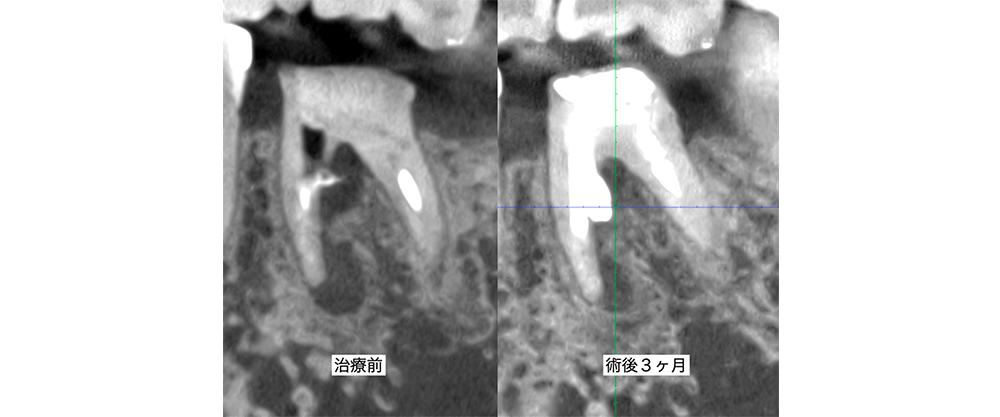

金山デンタルクリニックでは、治療の前に必ずCT撮影を行い、神経の本数や根の形、病変の大きさを正確に診査。治療の可能性や成功率まで含め、CTの画像を見せながら丁寧にご説明しています。治療後の経過もマイクロスコープやCT画像をお見せしながら、ご説明させていただきます。